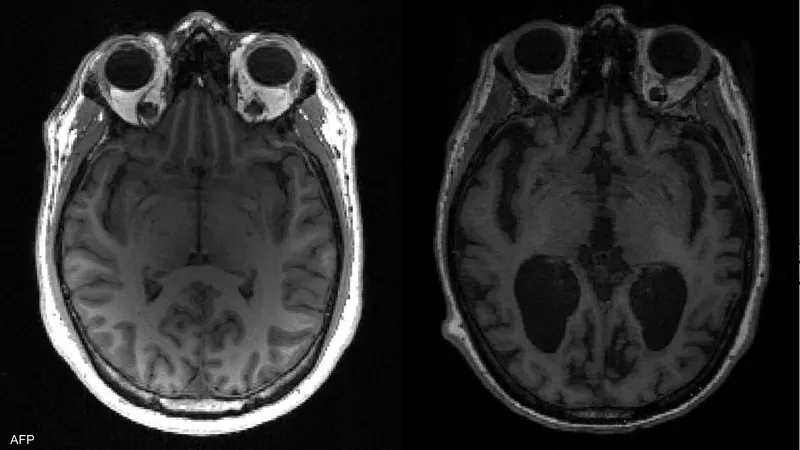

تمكن باحثون من تحديد خلايا قد تكون سامة أطلقوا عليها اسم “خلايا الزومبي”، في أدمغة الأشخاص الذين توفوا بعد إصابتهم بمرض ألزهايمر.

وأجرى زاري وزملاؤه اختبارات على 140 ألف خلية من 76 دماغا، وتوصلوا إلى أن أدمغة الذين ماتوا وهم يعانون ألزهايمر كانت لديهم مستويات عالية من لويحات “بيتا أميلويد” والبروتين “تاو”، التي تراكمت في الدماغ.